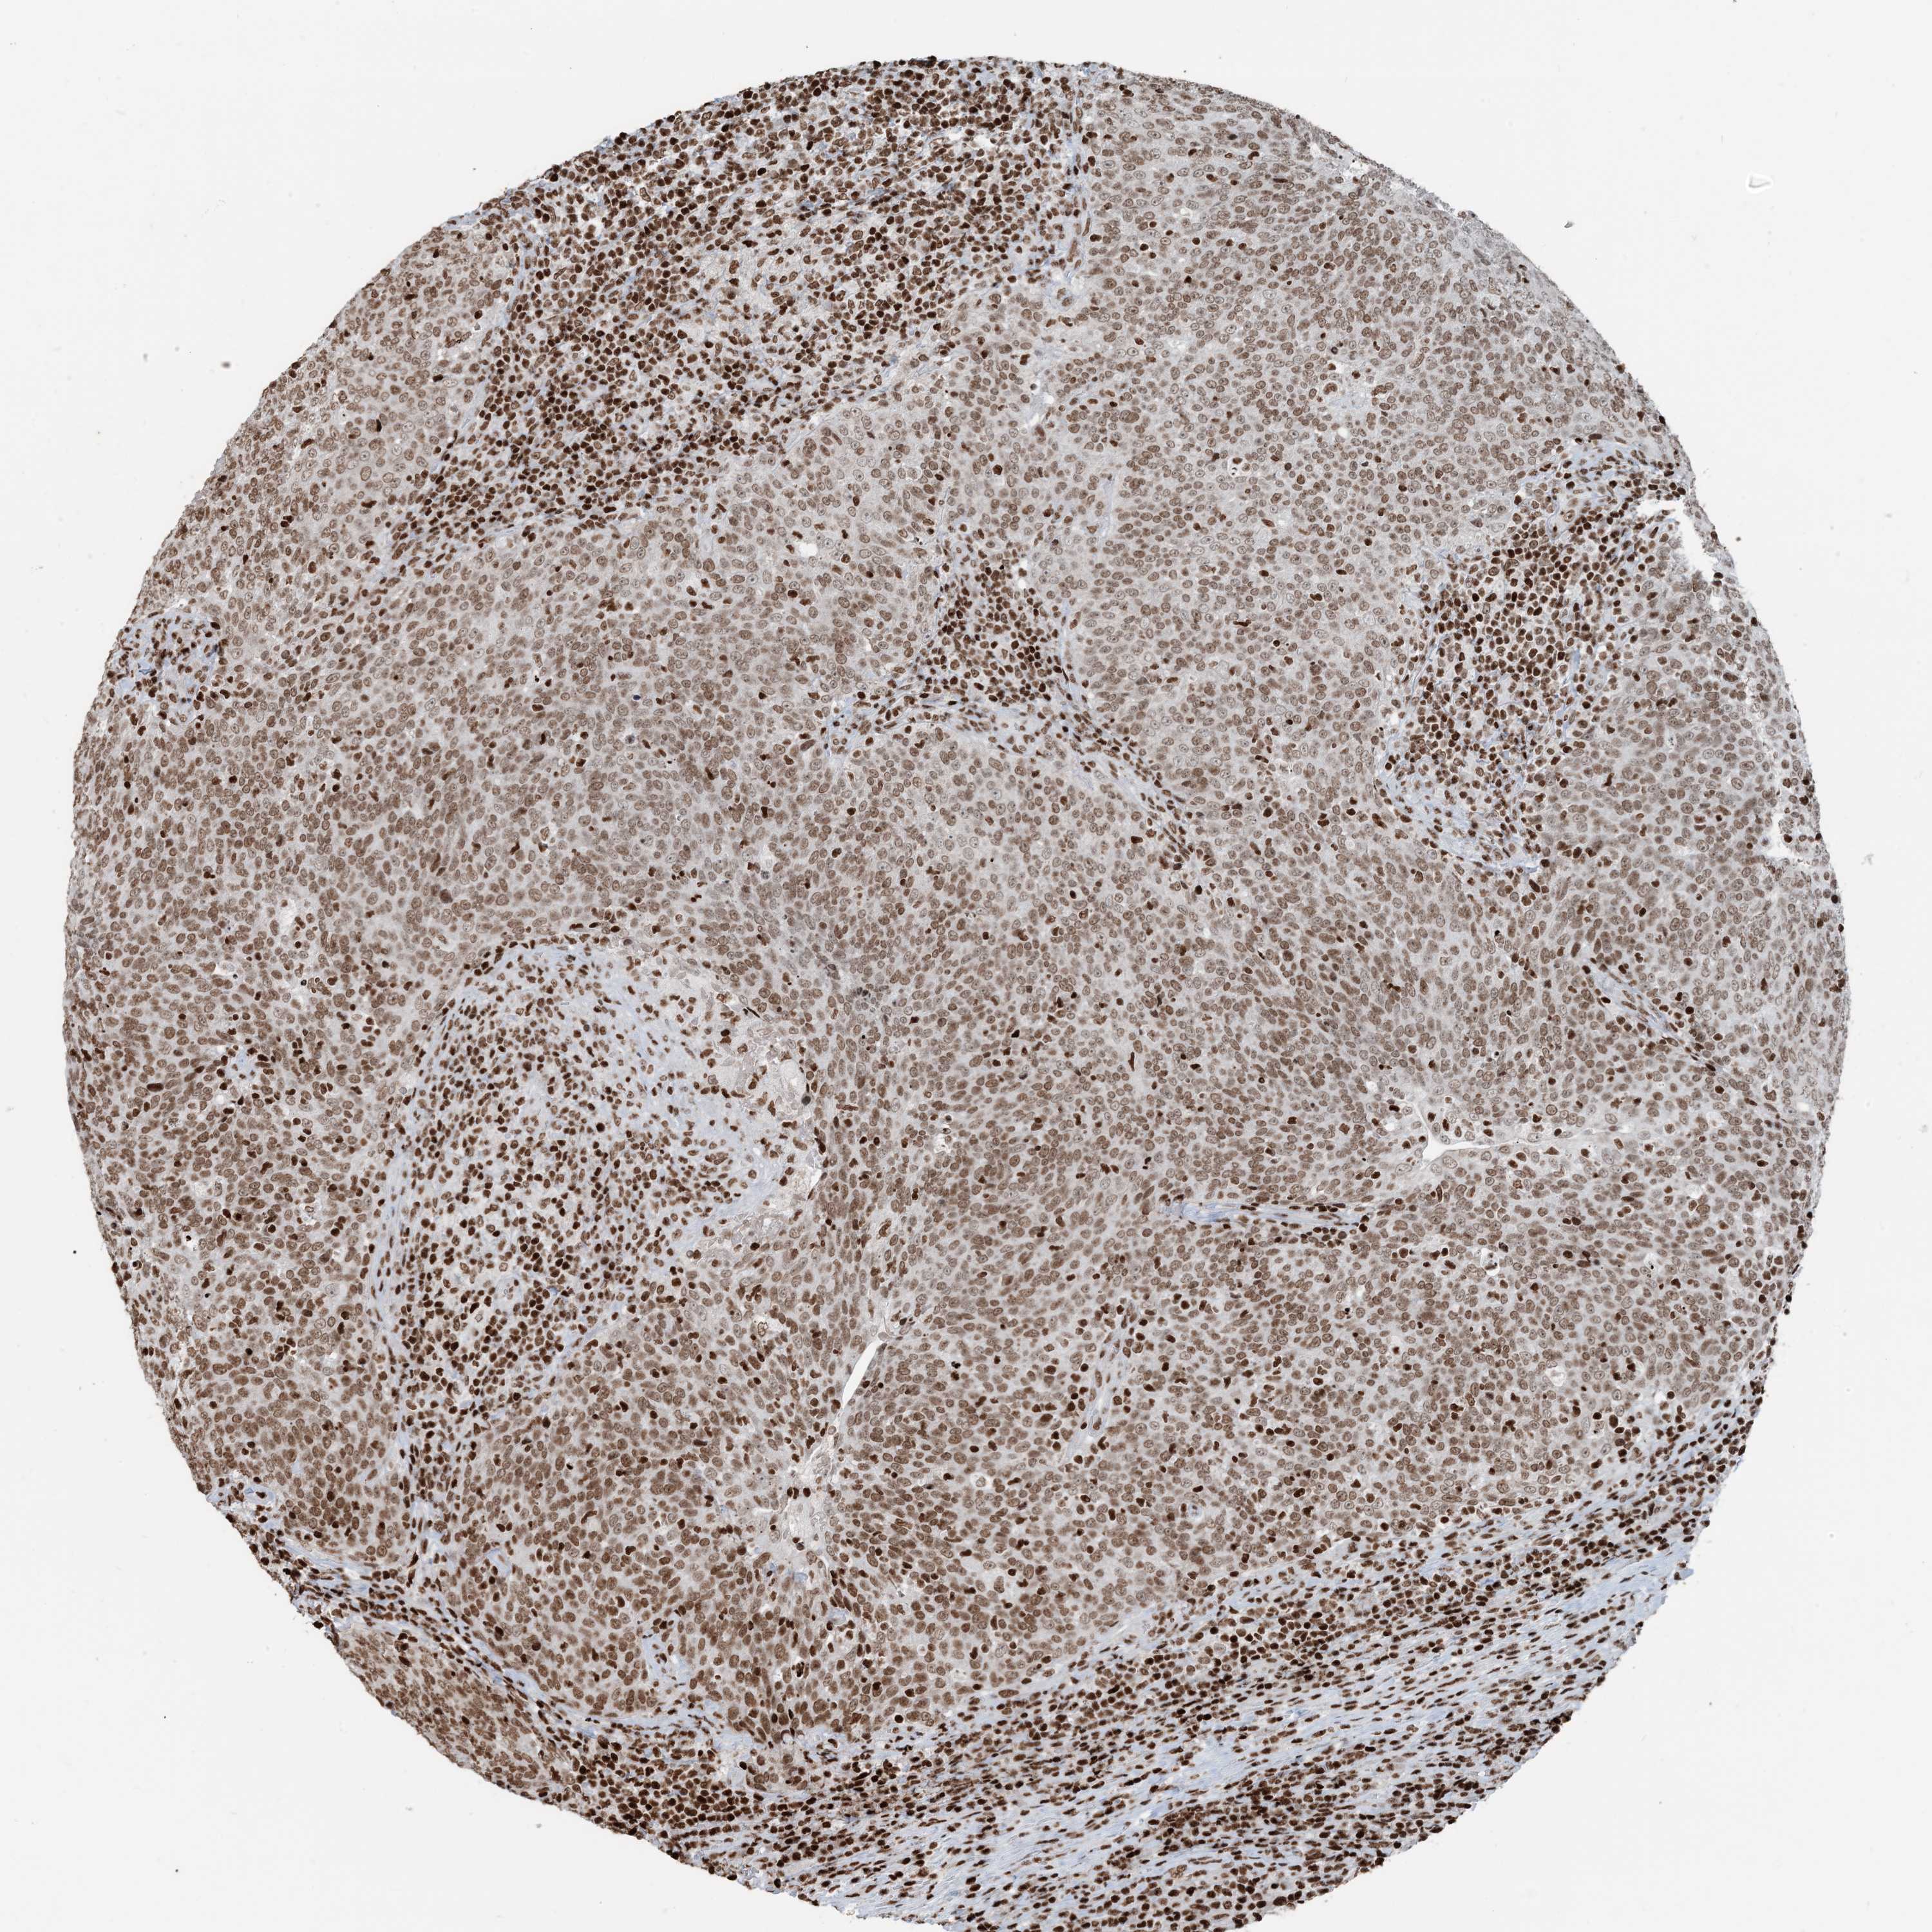

HEAD AND NECK CANCER - Protein expressioni

A mouse-over function shows sample information and annotation data. Click on an image to view it in a full screen mode. Samples can be filtered based on level of antibody staining by selecting one or several of the following categories: high, medium, low and not detected. The assay and annotation is described here.

Antibody stainingi

Antibody staining in the annotated cell types in the current human tissue is reported as not detected, low, medium, or high, based on conventional immunohistochemistry profiling in selected tissues. This score is based on the combination of the staining intensity and fraction of stained cells.

Each image is clickable and will lead to virtual microscopy that enables deeper exploration of all samples and also displays staining intensity scores, fraction scores and subcellular localization as well as patient and tissue information for each sample.

Antibody HPA042570

Antibody CAB037166

Antibody CAB037187

Antibody CAB037221

Staining

High

Medium

Low

Not detected

Intensity

Strong

Moderate

Weak

Negative

Quantity

>75%

75%-25%

<25%

None

Location

Nuclear

Cytoplasmic/membranous

Cytoplasmic/membranous,nuclear

Squamous cell carcinoma, NOS

Adenocarcinoma, NOS

Squamous cell carcinoma, metastatic, NOS

Adenoma, NOS